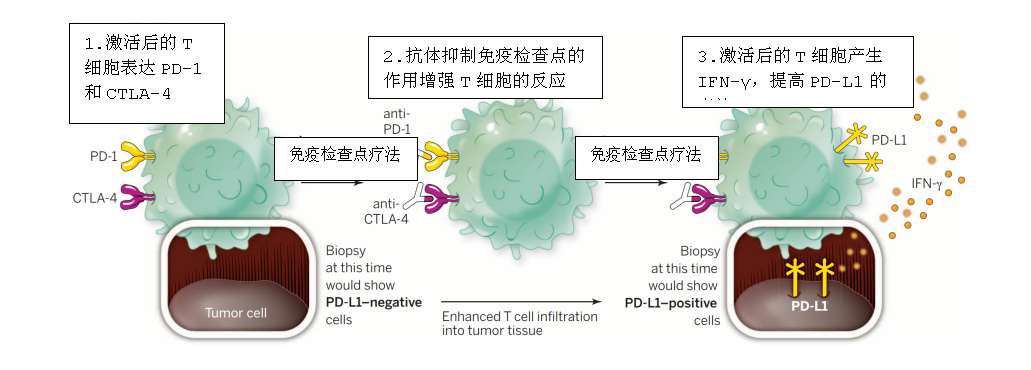

免疫治疗,尤其是免疫检查点抑制剂治疗,可以有效恢复T细胞消灭癌细胞的能力,从而给患者带来显着和持续的临床反应。不过,越来越多的研究证明,仅有一部分患者能从治疗中获益,大部分患者对这种疗法还是不响应。

免疫治疗示意图

免疫治疗示意图